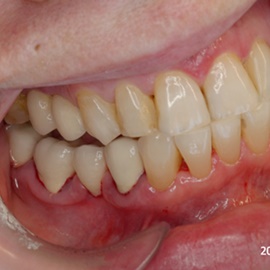

Przedtrzonowce często należą do okolicy estetycznej należy więc zwrócić wzmożona uwagę na poprawną anatomię tkanek kości i dziąsła. Po utracie zęba 25 pacjentka kilka lat chodziła bez jego uzupełnienia, doszło do przesunięcia się zęba 26. U tej pacjentki przed laty był wykonany most jednobrzeżny na czwórce, dość szybko doszło jednak do przeciążenia zęba filarowego, zaniku kości wyrostka i wreszcie pęknięcia korzenia zęba filarowego mostu. Po ekstrakcji i wygojeniu kości stwierdzono ubytek kości wyrostka przekraczający objętość 50% stanu początkowego. Stąd główny nacisk położono na odbudowę tkanek. Uzyskano zadowalający wynik anatomiczny.

Pacjentka lat 41, odbudowa protetyczna zębów 24, 25 na implantach - korony porcelanowe na metalu. Po stronie prawej zdjęto most 13 - 16, poprawiono warunki kostne wyrostka zębodołowego i wykonano most na implantach od czwórki do szóstki, oraz nacementowano pojedynczą koronę na kła.

Pacjentka lat 50. Most od zęba 24 do zęba 27. Pękł korzeń zęba filarowego 24. Po ekstrakcji wykonano zabieg odbudowy kości wyrostka zębodołowego i podniesiono zatokę. Następnie po skorygowaniu kształtu i objętości dziąsła przytwierdzonego wykonano pojedyńcze korony na implantach 24, 26, oraz most 13-17